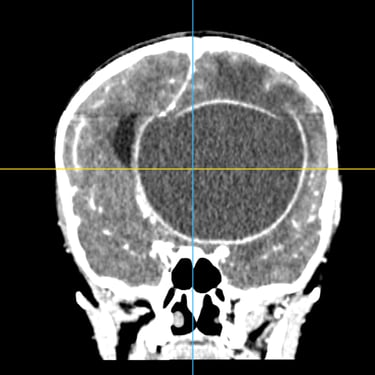

El absceso cerebral es una infección localizada del parénquima cerebral que produce acumulación de pus e inflamación, generando cefalea, fiebre, alteración del estado de conciencia o déficit neurológico focal. El diagnóstico temprano es fundamental para evitar complicaciones graves. La tomografía cerebral con contraste es el estudio de elección inicial, ya que permite visualizar una lesión hipodensa con realce en anillo característico. Posteriormente, la resonancia magnética complementa la evaluación. El tratamiento combina antibioticoterapia dirigida y, en casos seleccionados, drenaje quirúrgico o resección. La detección oportuna mediante imágenes mejora significativamente el pronóstico del paciente.